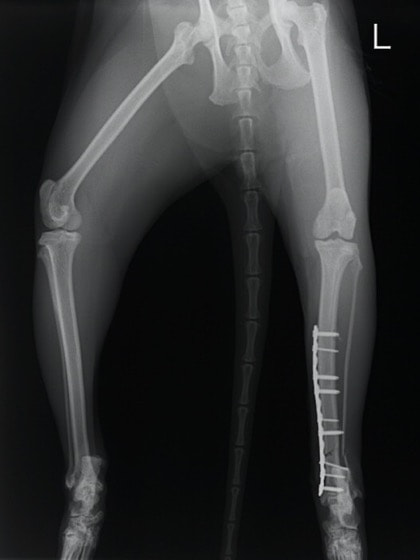

症例3:キルシュナーワイヤーのピンニングによる整復

ペルシャ猫 11ヶ月齢 雄

他院にて左大腿骨遠位の成長板骨折(salter-harrisⅠ型)が認められており、治療相談を目的として来院。当院にて、キルシュナーワイヤーを用いたピンニングにより骨折部位の整復を行いました。術後の経過は良好で、現在も経過観察中です。

術前レントゲン

術後レントゲン